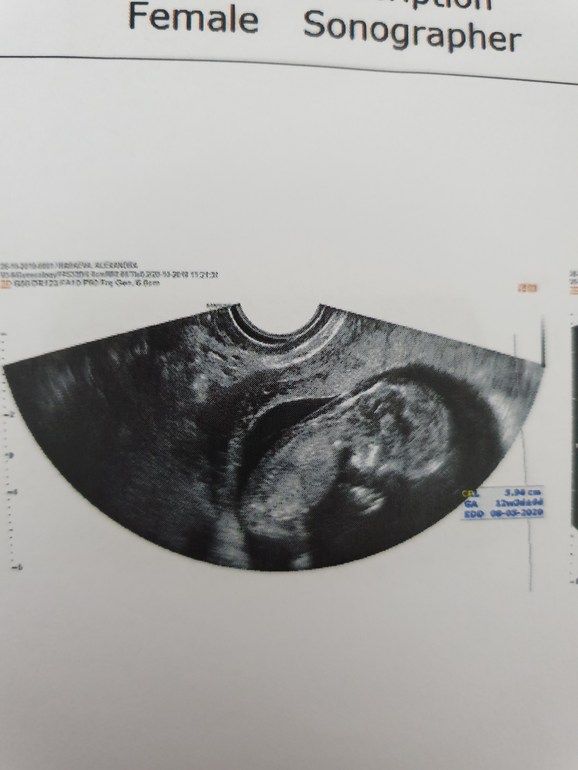

12+ 4 ! Скрининг, ощущения , фото 😍

Результаты: УЗИ, КТГ, доплера, скринингаНу вот, дождалась я этого скриринга! В первую Б не делала его и даже не собиралась делать, а тут дождаться не могла! И так!

По УЗИ все хорошо- как мы выросли за неделю!!! Догнали сроки. По развитию поставила пдр 7 мая, если ПКС то 1 мая. Любовалась малышастиком минут 30🤗 все разглядели, и ручки, и ножки ,и УшкИ😍 поспал, покрутился, головку почасал, дал полюбоваться собой со всех сторон ❤

А вот и мы